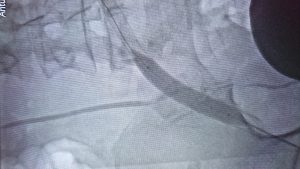

Girişimsel yöntemlerin hepsi anjiografi salonunda, lokal anestez altında ve herhangi bir kesi yapılmadan uygulanır. Hastanede yatış süresi ve iyileşme süreci, cerrahi tedaviye göre daha kısadır. Bununla birlikte işlem yapılan damarlarda erken veya geç dönemde tekrar darlık oluşma veya tıkanma riski bulunmaktadır.

• Stent İmplantasyonu : Özellikle kasığın üstünde yer alan atardamarlarda ve zaman zaman da bacak atardamarlarında kullanılan bir yöntemdir. Dizaltı damarlarda zorda kalınmadıkça kullanılması önerilmez. Tamamen metal yapılı olan stentler ve içi vücutla uyumlu çeşitli yapıdaki materyallerle kaplı stent greftler bulunmaktadır.